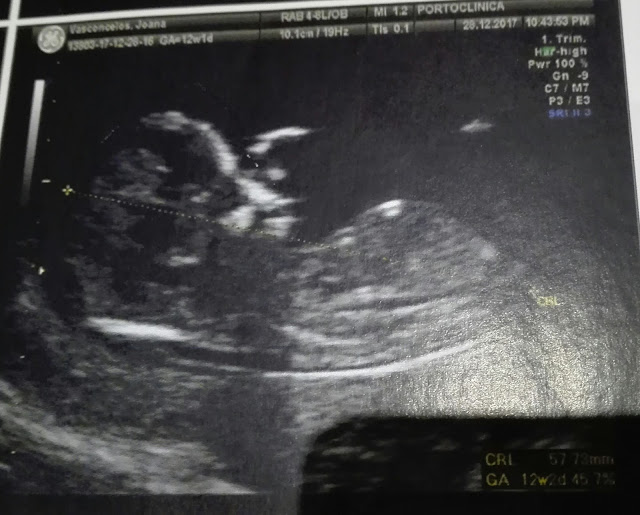

Foi no dia 28 de dezembro, que fomos fazer uma das ecografias mais emocionantes.

Saber se o nosso bebé estava a formar-se bem, se estava tudo bem com a formação de órgãos e membros e se os índices de cromossomas estavam bem.

E graças a deus estava tudo bem.

O bebê não parava quieto e a Dra não conseguia tirar um batimento cardíaco perfeito mas depois lá conseguiu. 😊

O engraçado desta ecografia é que o bebé estava com a mão no nariz. 😂

Se repararem bem nas ecografias dá para ver. 😊